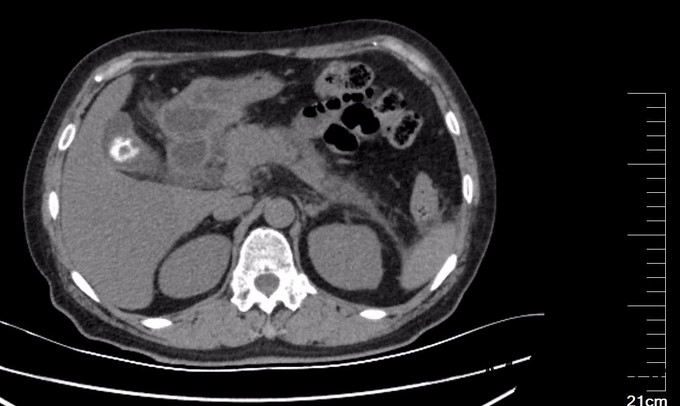

查体: 腹平坦,未见胃肠型及蠕动波,腹软,右上腹压痛明显,伴反跳痛,无肌紧张,肝脾肋下未扪及肿大,无移动性浊音,双肾区无叩痛,肠鸣音存在。 辅查:超声检查: 胆囊大小约6.1x2.4cm,壁厚约0.3cm,囊内见多个强回声团,较大者直径约0.9cm,声影(+),移动(+)。 胰腺轮廓模糊,胰腺头、体厚度分别为2.4cm、2.6cm,回声粗糙,主胰管直径约0.1cm。胰尾部受肠气干扰显示不清。 腹腔未见明显积液影像。 CT提示:肝内外胆管未见明显扩张,胆囊壁稍厚,内见结节状高密度影,直径约1.9cm。胆总管下段细点状高密度影,大小约0.2cm,胰腺边界模糊,周围多发条状絮状渗出影,双肾前筋膜增厚,十二指肠管壁模糊。血淀粉酶(AMY)、血脂肪酶(LPS )及尿淀粉酶(Amy-U)明显增高(见图里化验报告)。